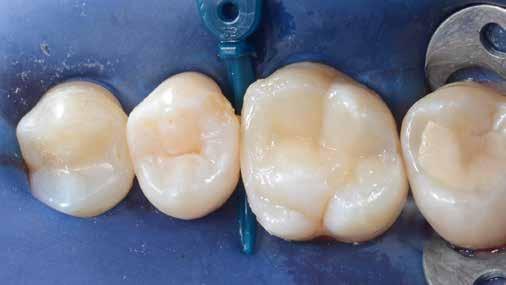

4. ábra: A durva finírozás után a restauráció pereme sima és anatómiailag is megfelelő.